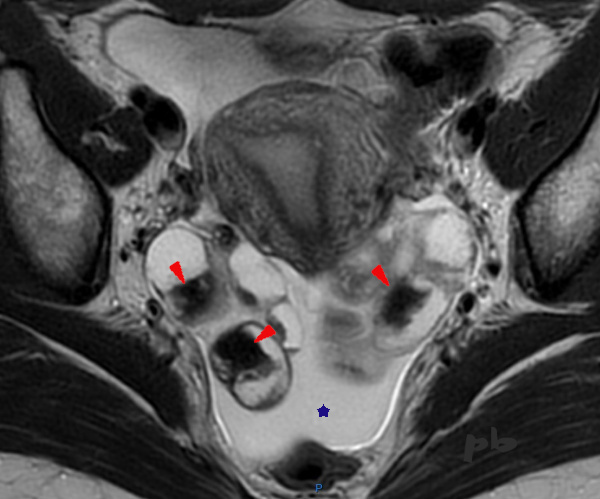

17 – Diagnostic différentiel IRM – Saignement intra-folliculaire

IRM coupe axiale T2.

L’IRM est réalisée dans le cadre d’un bilan d’endométriose profonde.

Mise en évidence de multiples images liquidiennes ovariennes bilatérales, en hypersignal, dans lesquelles on retrouve des zones irrégulières en franc hyposignal, de type « shading » (►).

L’interrogatoire permet d’apprendre que la patiente vient de bénéficier d’une stimulation ovarienne en vue d’une FIV, avec ponction folliculaire le matin même de l’examen, expliquant l’ensemble des images.

Le sang récent est en franc hyposignal T2.

Par ailleurs, épanchement dans le Douglas (★).